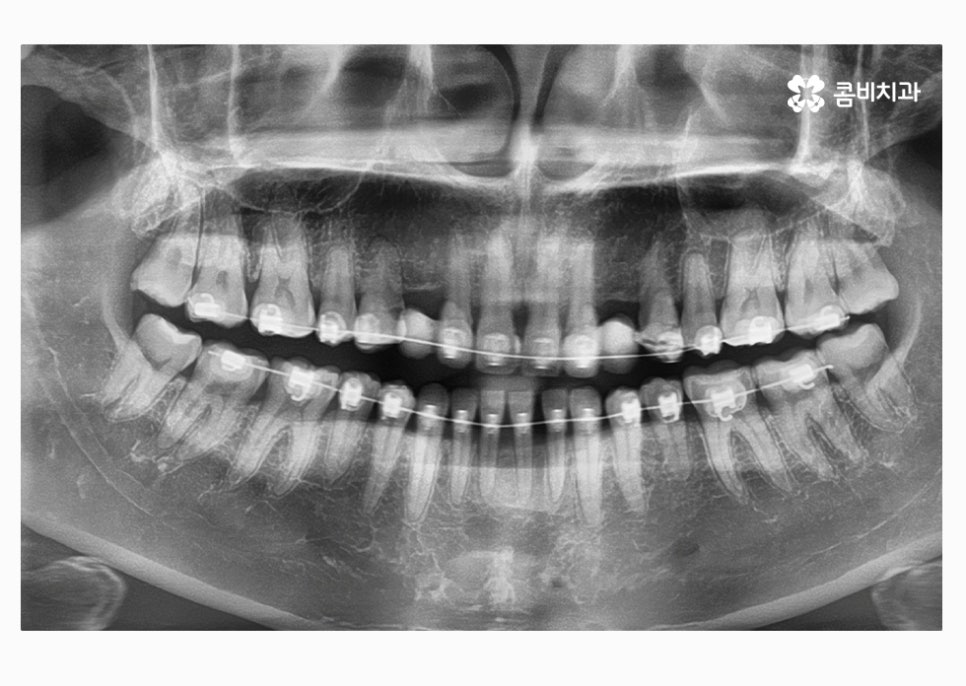

오늘 보실 30대임플란트 환자분의 사례는

윗니 2개를 충치로 인해 잃게 되어 임플란트를 하게 되었으며

아랫니가 벌어져 있고 치열이 고르지 못해서

치아 관리에 어려움을 느꼈기 때문에 치아 건강과

심미적인 치열을 위해서 치아교정도 함께 진행된 사례라고 할 수 있어요.

위에 표시된 치아는 이미 발치가 된 상태에서 임시치아를

부착하고 생활을 하셨던 환자이며 고르지 못한 치열을

개선하고 임시치아를 부착한 치아에 임플란트를 식립한 사례라고 할 수 있어요.

자세히 보시면 임시치아라는 것을 알 수 있고 엑스레이

사진을 보면 더 자세히 알 수 있습니다.